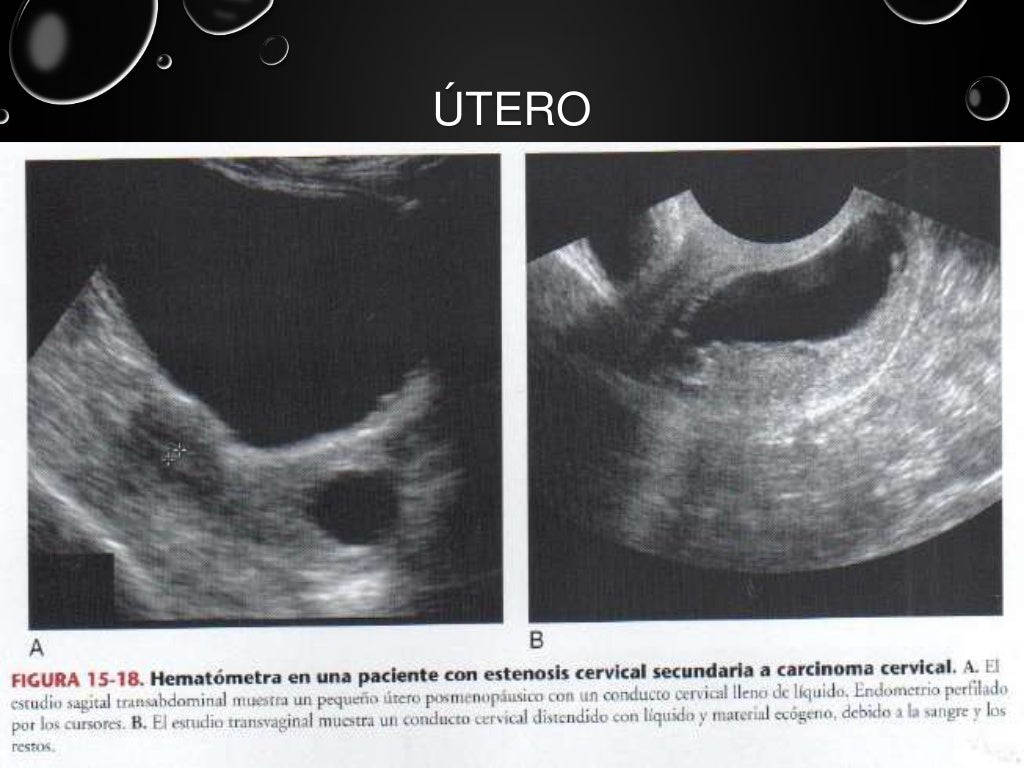

Ultrasonido pelvico

Source: es.slideshare.net